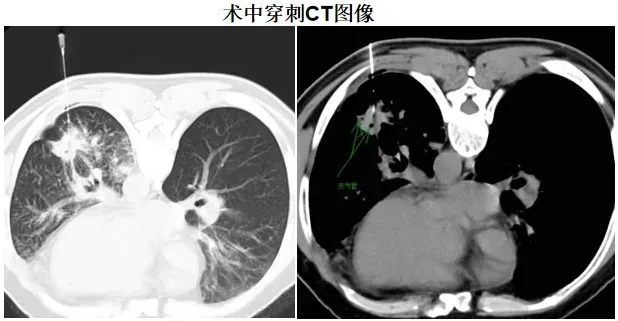

时间紧迫,分秒必争。当务之急便是获取肺部病变组织的病理结果,才能为后续的治疗指明方向。与患者家属充分沟通后,为患者实施了CT引导下经皮左肺病变穿刺活检术,手术团队凭借精湛娴熟的技术,成功获取了病变组织样本。经过严谨细致的病理检测,最终确诊为左肺腺癌。在全体医护人员的悉心照料与专业治疗下,患者病情迅速得到控制并好转,患者的脸上重新绽放出久违的笑容。